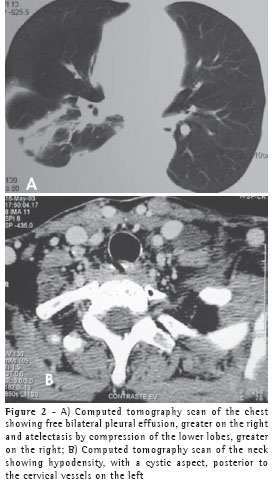

A previously healthy, 63-year-old female who was a nonsmoker and homemaker presented with swelling of the neck, anterior chest wall, abdomen and lower limbs. This was accompanied by discrete dyspnea upon exertion. The symptoms began after light physical activity at a fitness center five days prior. She reported no previous pulmonary disease and was taking 20 mg of fluoxetine per day, 3 mg of bromazepam per day, and regular female hormone replacement. Upon clinical examination, a discrete increase in volume was observed in the left supraclavicular fossa and in the right lateral neck wall. We also observed a diffuse decrease in breath sounds and in vocal fremitus in the lung bases (greater on the right than on the left), as well as edema in the anterior abdominal wall (grade 1) and in the lower limbs (grade 4).We requested the following tests: blood workup, coagulation profile, blood glucose, creatinine, urea, erythrocyte dissemination, total cholesterol, HDL, triglycerides, triiodothyronine, thyroxine, thyroid-stimulating hormone, and partial urinalysis, all of which presented normal results, ruling out dyslipidemia, coagulopathy, infection, nephropathy and hypothyroidism. Radiological evaluation of the thorax revealed slight bilateral pleural effusion (Figure 1), which was confirmed through a computed tomography scan of the chest (Figure 2A). This was complemented with tomography slices acquired at the neck level, revealing edema in the left supraclavicular region with hypodensity (20 × 10 mm) adjacent to the neurovascular bundle of the neck (Figure 2B).